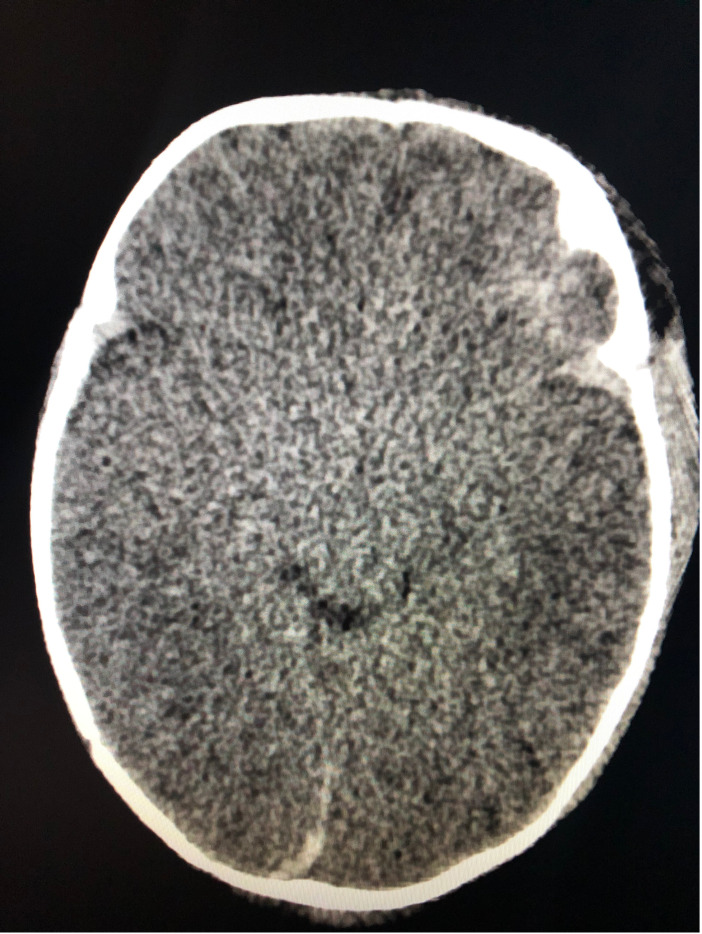

Background: Point of Care Ultrasound (POCUS) is an important tool in pediatric emergency medicine. In neonatal intensive care medicine ultrasound is often used to evaluate the brains of sick neonates. In theory, POCUS could be used in the ED in young children to evaluate the brain for abnormal pathology. Objectives: To examine the ability of PEM faculty to use brain POCUS to identify clinically significant brain injuries in children with head injuries and/or abnormal neurological exams, and generate sensitivity and specificity of brain POCUS in assessing such findings. Methods: This study used a convenience sample of patients seen in a tertiary care pediatric centre who required a CT head. A team of physicians who were trained at a workshop for brain POCUS were on call to perform the POCUS while being blinded to the results of the CT. Results: 21 children were enrolled in the study. Five (24%) of the patients had a CT that was positive for intracranial bleeds. Of the 5 patients with a positive CT, 3 had a brain POCUS scan that was also positive. The two false negative brain POCUS scans were on patients with small bleeds (no surgical intervention required) on CT, as reported by radiology. The sensitivity of brain POCUS was 60% (CI 15% - 95%) with a specificity of 94% (CI 70%-100%). The diagnostic accuracy of brain POCUS was 86% (CI 64% - 97%). Conclusion: This small proof of concept study shows that brain POCUS is an imaging modality with reasonable sensitivity and specificity in identifying intracranial pathologies that are present on CT. Its use may be most beneficial to expedite definitive imaging and subspeciality involvement.

Abstract Image